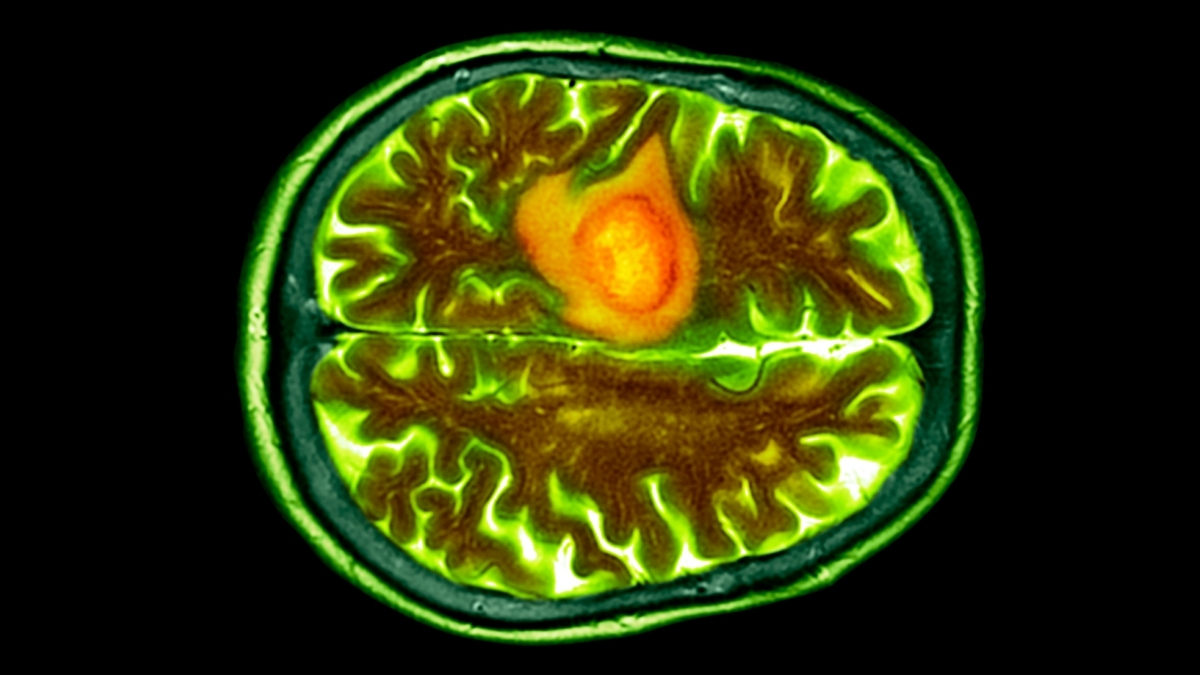

Tədqiqatçılar, burun damcıları vasitəsilə beyinə çatdırılan və mərkəzi sinir sistemi daxilində glioblastoma adlı ən təhlükəli beyin xərçəngi növü ilə mübarizə aparan yeni bir dərman inkişaf etdiriblər. İlkin test nəticələri göstərir ki, dərman hədəfinə təhlükəsiz şəkildə çataraq, siçanları bu adətən ölümcül şişlərdən qorumağa kömək edib. Bu yenilik, burun damcıları ilə beyinə dərman çatdırılmasının potensialını ortaya qoyur. Vaşinqton Universitetindən neyrocərrah Aleksandr Steq bildirib: "Bu yanaşma, glioblastoma və digər immunitet müalicəsinə davamlı xərçəng növləri üçün daha təhlükəsiz, daha effektiv müalicələrə ümid verir və klinik tətbiqə doğru kritik bir addımdır." O əlavə edib ki, bu, əlçatmaz şişlərdə xərçəng immunoterapiyasının necə həyata keçirilə biləcəyini yenidən müəyyənləşdirir.

Glioblastoma şişləri yüksək dərəcədə aqressivdir, erkən aşkarlanması çətindir və orqanizmin tipik immun reaksiyasını deaktiv edir. Bu xüsusiyyətlər, onları ənənəvi xərçəng müalicələri ilə hədəf almağı çətinləşdirir. Həm də beynimizdə və ya mərkəzi sinir sistemimizin digər hissələrində əmələ gəldiyi üçün əlçatmaz olurlar. Bu amansız xərçəng növü, ətrafdakı sağlam toxumalarda şişkinliyə səbəb olmaq, onları sıxmaq və qan tədarükünü oğurlamaqla beyin funksiyalarını zədələyir.